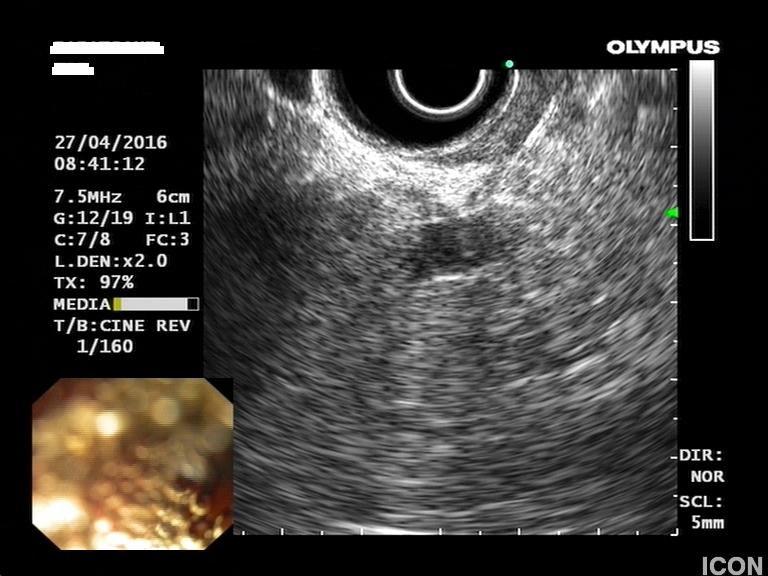

Δεύτερη μικρότερη κύστη στο σώμα του παγκρέατος